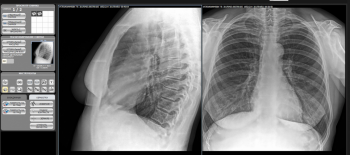

Мы провели тестирование в области цифровой рентгенодиагностики в медицине и пришли к выводу, что высокое качество изображения не всегда можно получить, используя стационарное рентгеновское оборудование. Если использовать рентгеновский приёмник с PSA модулями и математической обработкой изображения, то можно получить чёткое изображение при низкой дозе облучения, как для пациента, так и для врача.

Рекомендуем ознакомиться с качеством изображения.